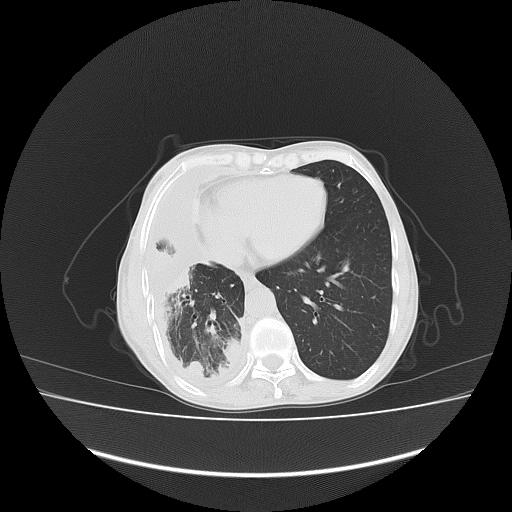

可见多发肺内病灶,且胸膜病灶较多有圆球状而非丘状,多考虑胸膜转移瘤伴胸腔积液,右侧胸廓缩小固定,且部分病灶呈丘状,尚不除外恶性胸膜间皮瘤伴肺内转移

恶性胸膜间皮瘤伴肺内转移可能性大;或胸膜、肺内均为转移瘤,左肺下叶亦见多发小结节影。

右侧胸膜转移瘤,原发灶可能就在在右肺,另外建议检查右侧乳腺.

胸膜转移瘤  包裹性胸腔积液  肺内转移

右胸腔结节均考虑来自胸膜(部分来源于叶裂),考虑胸膜间皮瘤或转移瘤.